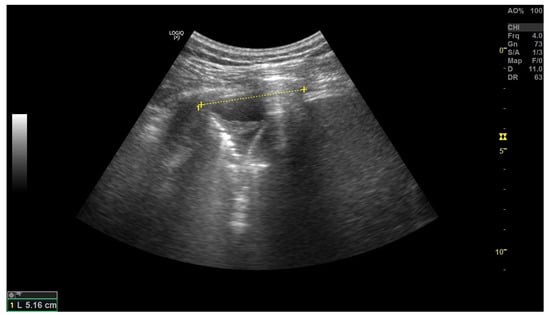

3.2. Inferior Vena Cava Measurement